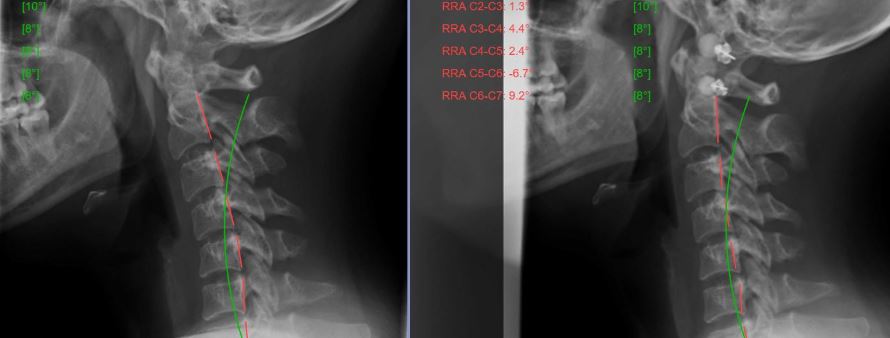

But…what about preventing cervical disc herniations, wear-and-tear arthritis, pain and disability? A recent study published in the Journal Medicine (August 2019) again confirmed that abnormal spinal alignment and posture, specifically a loss of normal curve in the neck, has significant health consequences.

“…the degree of disc herniation and height of disc space can recover with the recovery of cervical lordotic curvature…indicating a link between cervical curvature and degenerative changes which have important clinical implications.”

“With the improvement of cervical lordotic curvature (neck curve), the degree of disc herniation decreased and the height of disc space increased.”